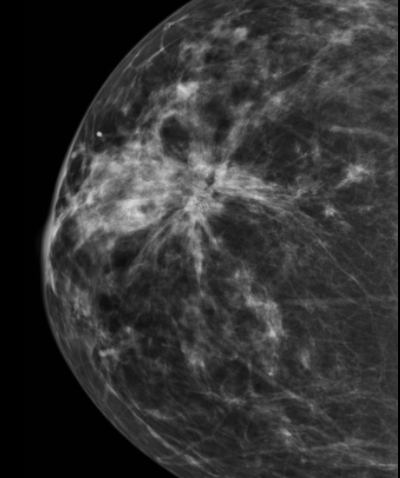

• Distortion architecturale spiculé sans vraie masse dense au centre

• A résequer car DCIS sous-jacents (40% a l’histo) ++

radial radiale scar